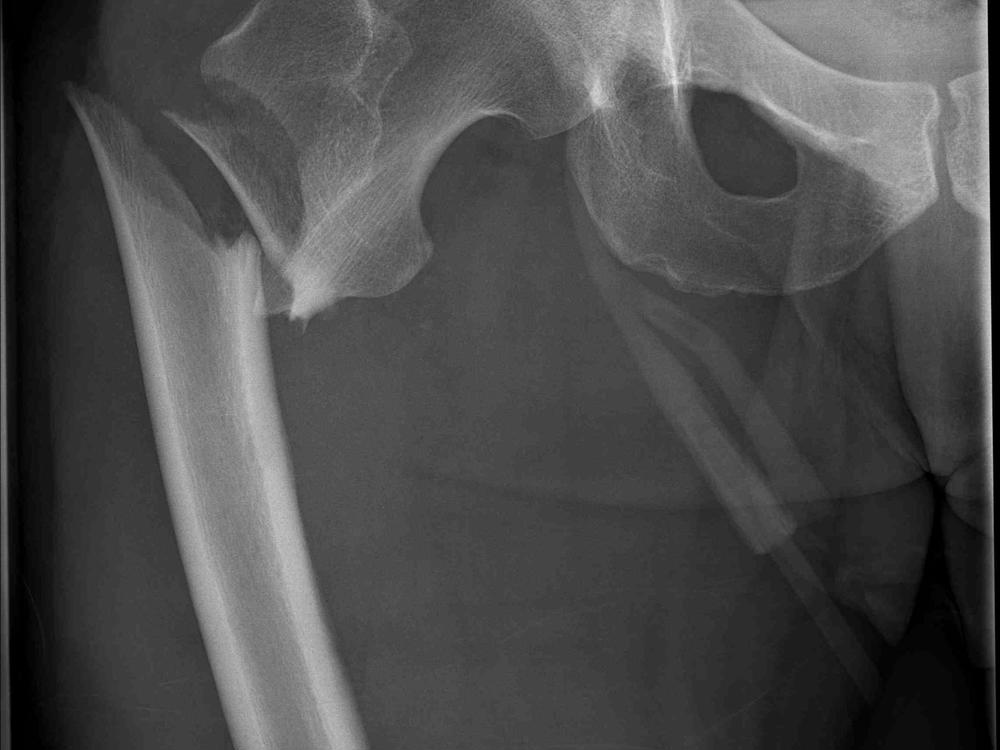

Broken femur

So unfortunately whilst I was out with locals I was unlucky on a wave and broke my femur preve, preventing preventing me from getting back in the water for a long time. I am asking for any donations to help with a speedy recovery through good rehab. Anyone who knows me will know this will help me continue to spread positive vibes in the water and share the the knowledge of our waters keeping people safe in the water

Not sure at this time as the injury occurred whilst in Samoa. Ongoing rehabilitation and further medical costs.

Healing taking longer than expected   20 August 2020

Unfortunately due to the severity of my break my rehabilitation is taking longer than expected. Due unforseen costs I would be much appreciative for any donations made.